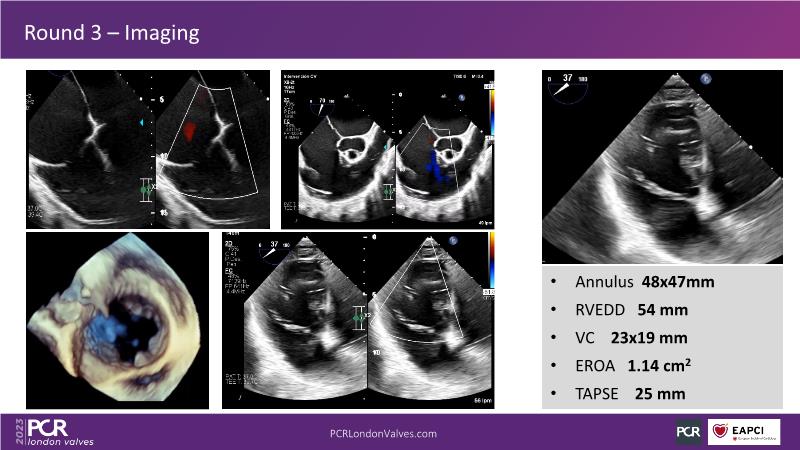

This session offers an opportunity to engage in a real case discussion led by an advanced Heart Team. Participate in discussions on controversial decision-making scenarios and stay informed about the latest clinical evidence related to MitraClip, Tendyne, and TriClip therapies.